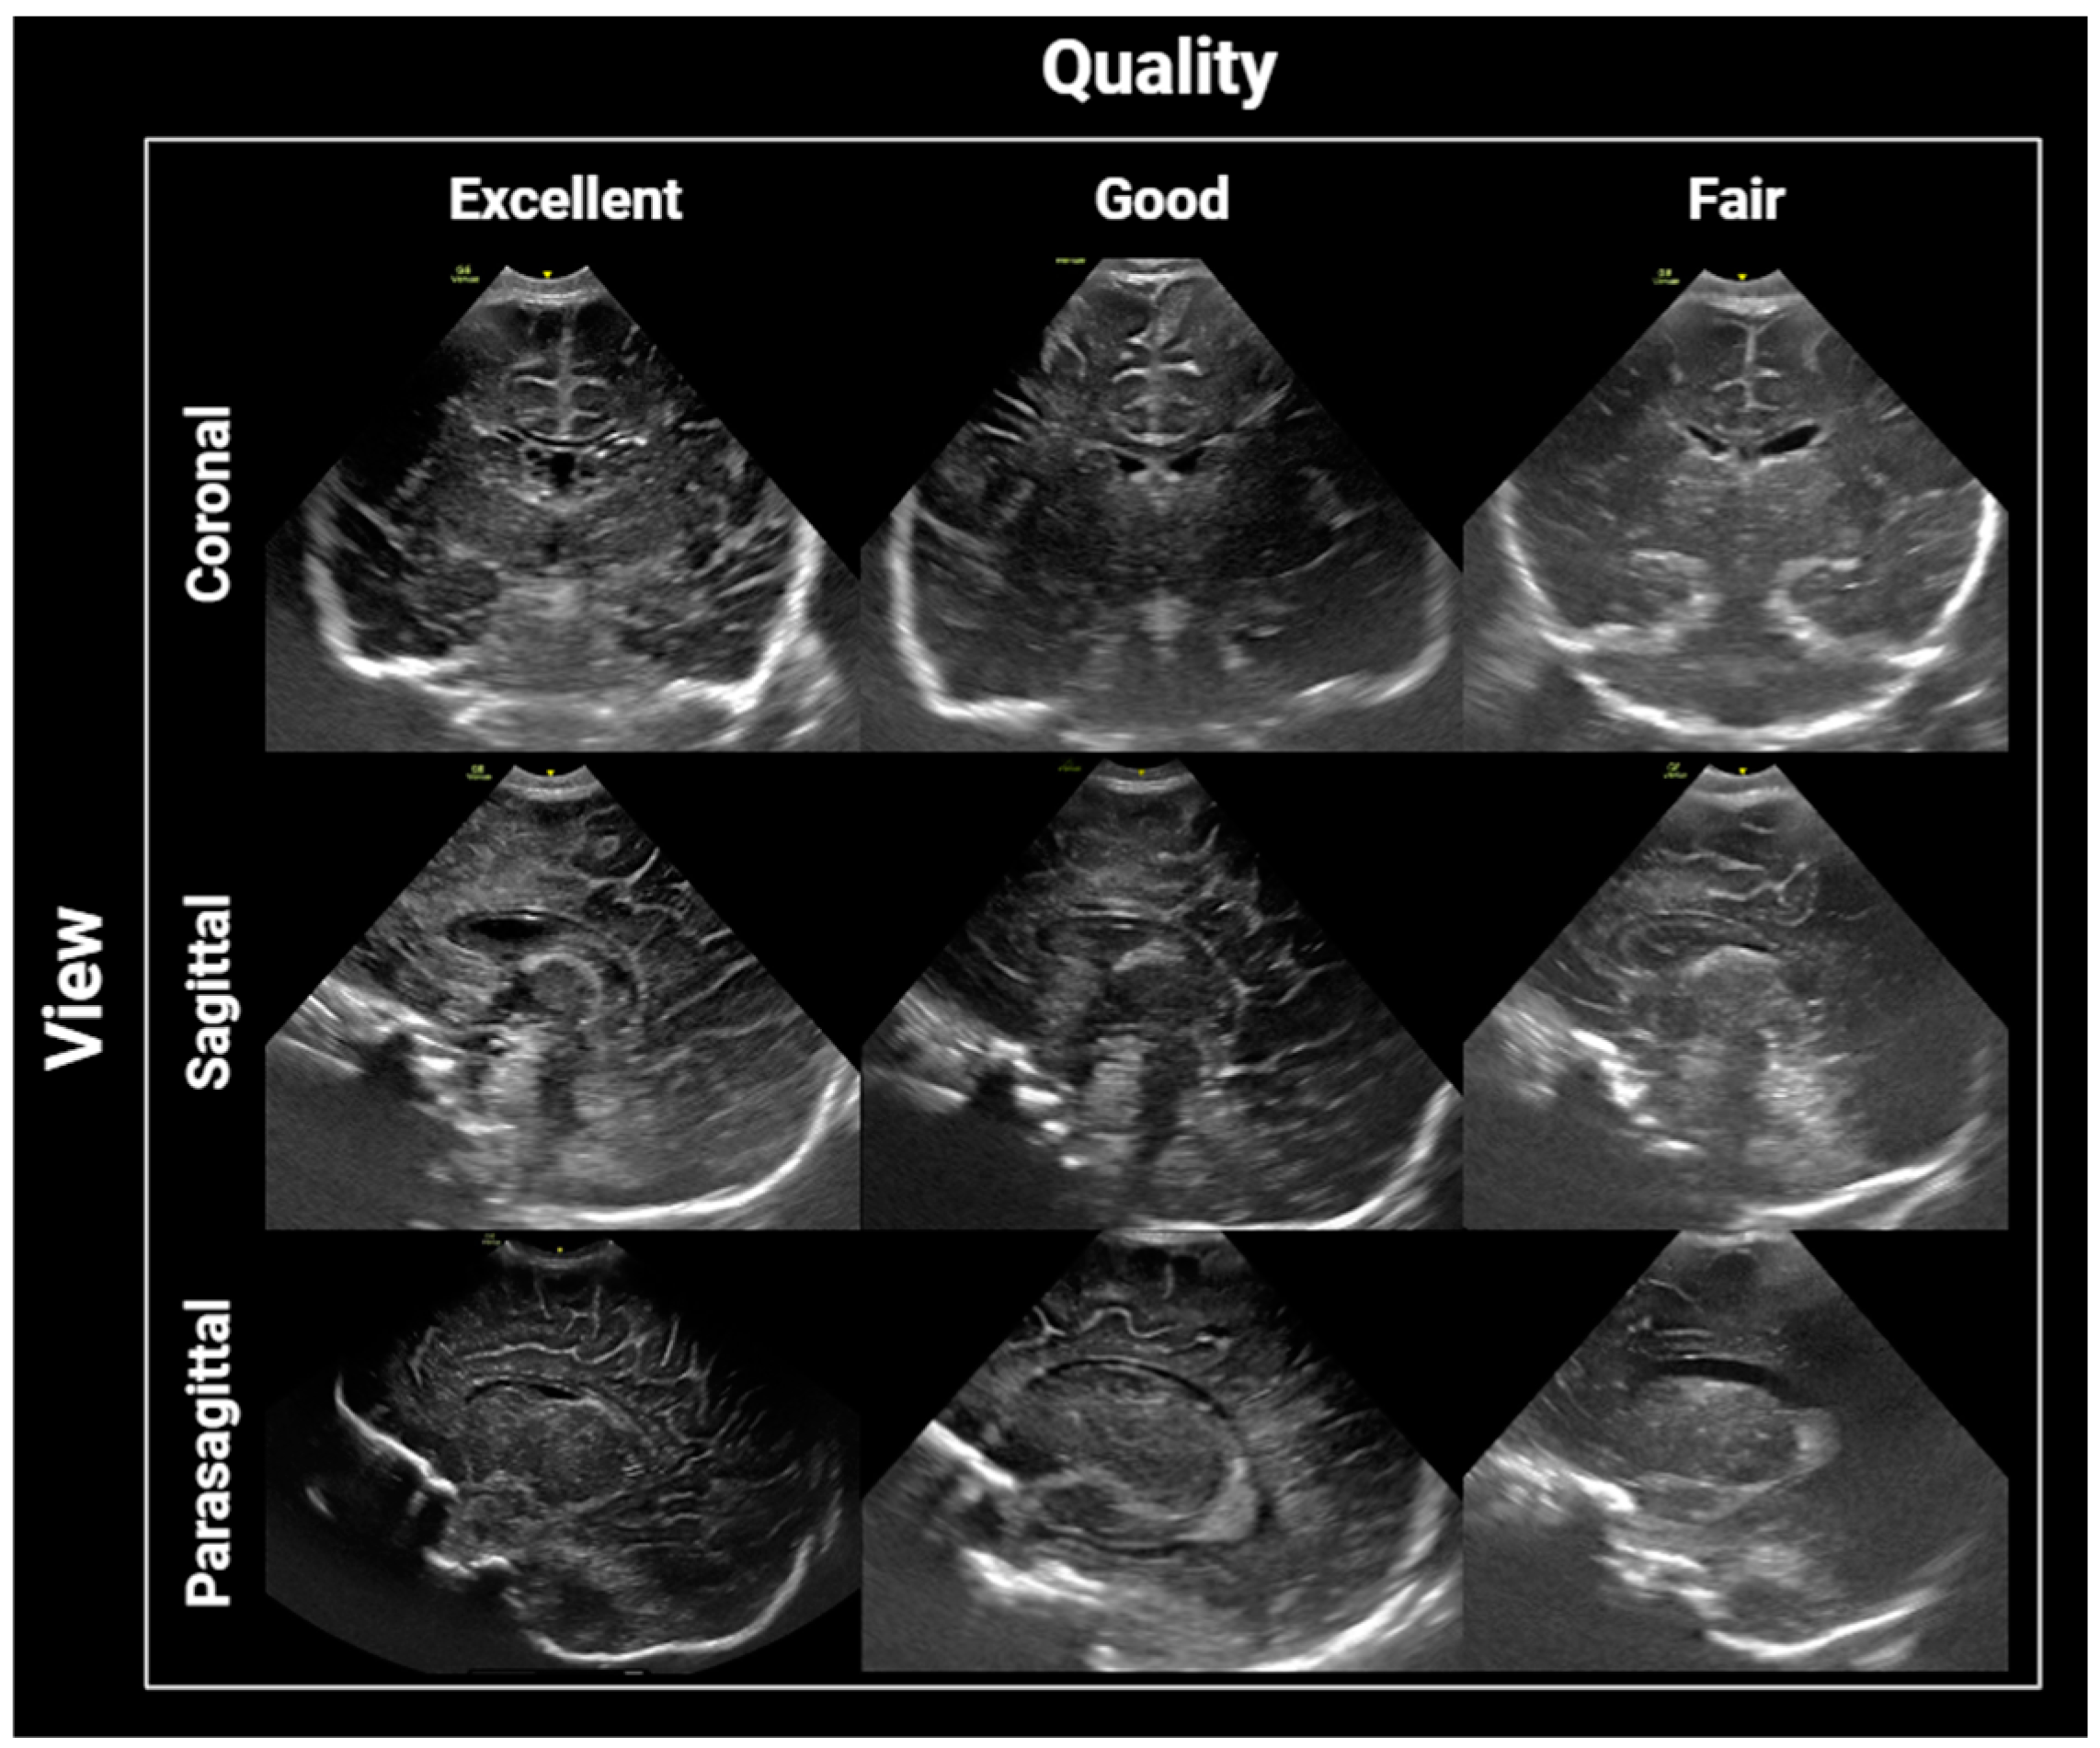

2.3. Brain US Protocol

2.4. Image Interpretation and Analysis